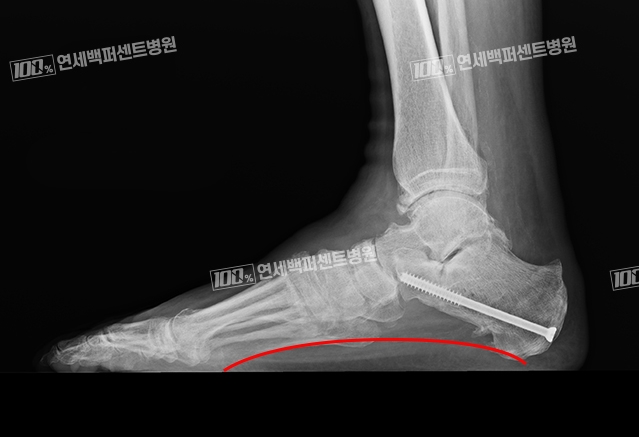

안쪽 아치를 만들어줌으로써 평발을 교정하는 수술법으로

발의 외측 복숭아뼈 하방에 나사를 삽입하여

발의 아치가 무너지지 않도록 발의 동작을 제한하는 수술입니다.

치료 후 다시 생긴 발아치

평발 관절제동술 후